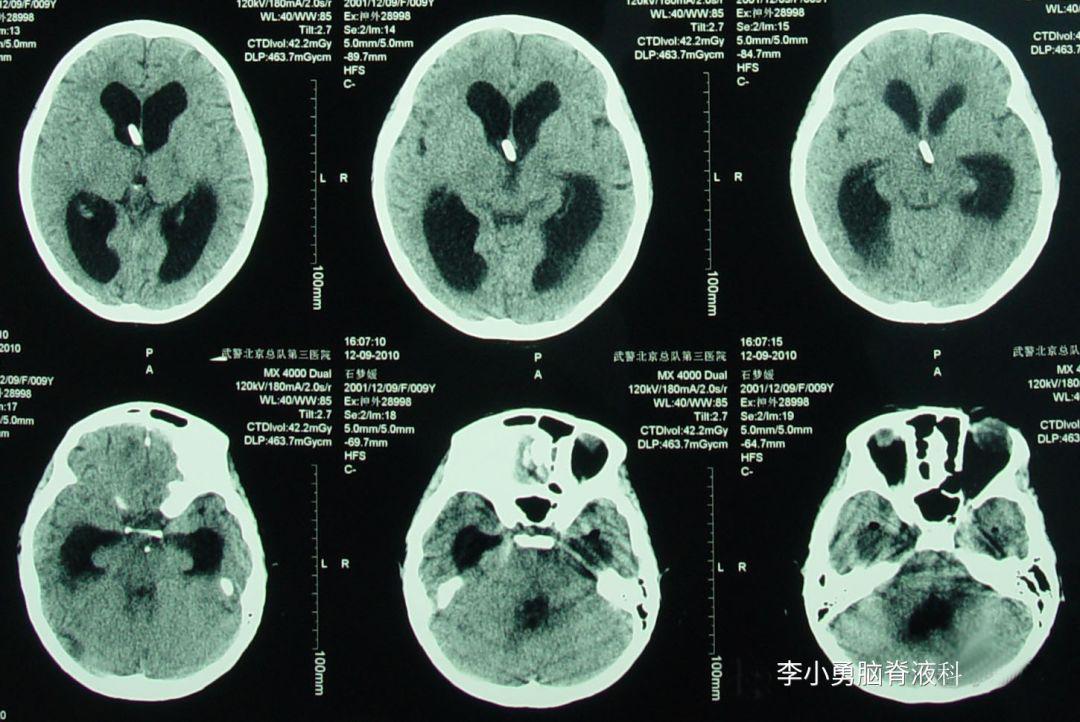

2010年12月2日(住院治疗3天),查头颅CT示脑室缩小(图-13)。

图-13:2010年12月2日头颅CT

2010年12月9日(住院治疗10天),查头颅CT示脑积水进一步变好(图-15)。

图-15:2010年12月9日